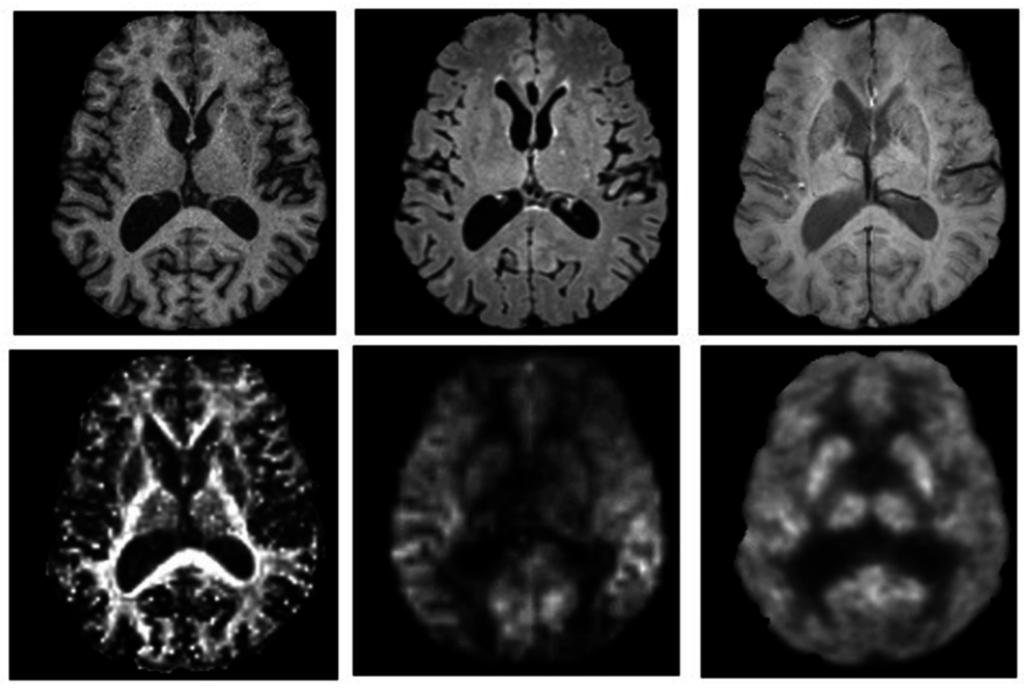

- Anazodo, U.C.; Thiessen, J.D.; Ssali, T.; Mandel, J.; Gunther, M.; Butler, J.; Pavlosky, W.; Prato, F.S.; Thompson, R.T.; St Lawrence, K.S. Feasibility of simultaneous whole-brain imaging on an integrated PET-MRI system using an enhanced 2-point dixon attenuation correction method. Front. Neurosci. 2014, 8, 434. [Google Scholar] [CrossRef] [PubMed]